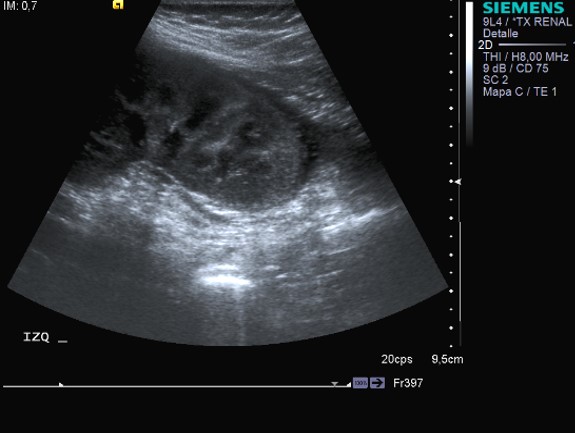

Hidronefrosis:

El diagnóstico ecográfico de la obstrucción se basa en la detección de dilatación del sistema colector.

Ecograficamente se reflejan como espacios anecoicos que sustituyen a los cálices e infundíbulos renales y hay varios grados de afectación, desde los leves hasta aquellos que pueden acabar con la función renal.

Alta afectación.